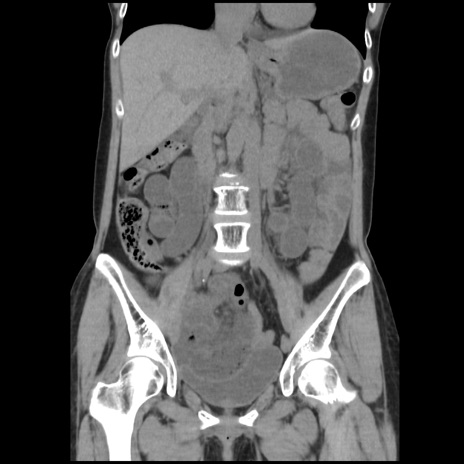

症例32(冠状断像)

【症例】40歳代 女性

【主訴】上腹部痛、嘔気・嘔吐

【現病歴】約9時間前頃から急に上腹部痛、嘔気、嘔吐が出現。改善しないため救急要請。

【既往歴】子宮頚癌(広汎子宮全摘術、放射線療法)、腸閉塞

【身体所見】腹部:平坦、軟、腸雑音亢進、上腹部を中心に腹部全体に圧痛あり。

【データ】WBC 8400、CRP 0.03